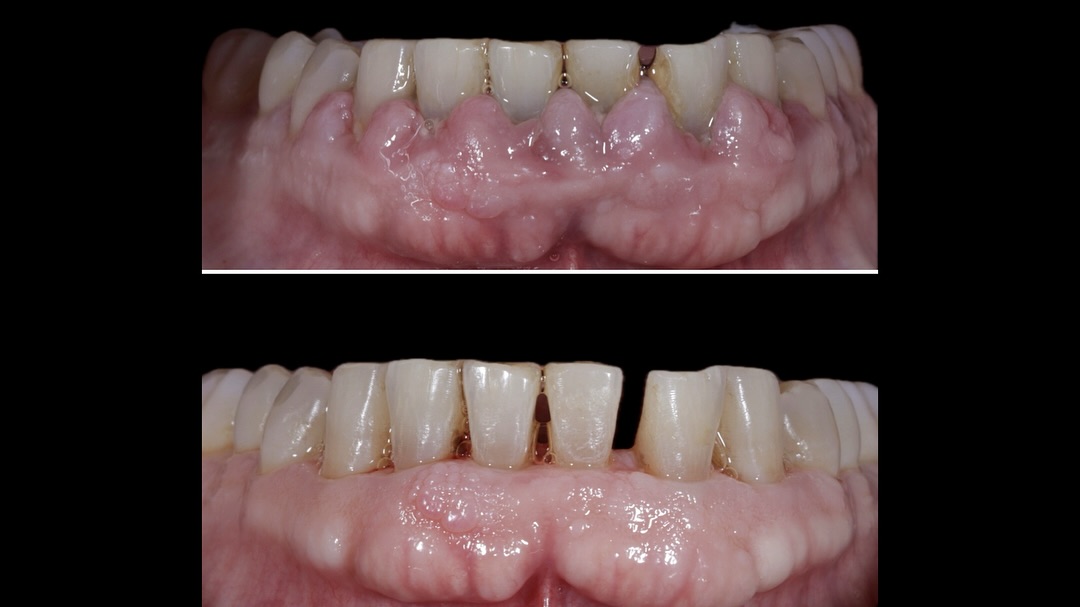

Se presenta un caso clínico de restauración directa en resina composite, ejemplo del valor de la precisión y la técnica meticulosa incluso en procedimientos considerados rutinarios dentro de la práctica diaria. El caso pone en evidencia la importancia del control de la morfología, la textura y la integración cromática, así como del adecuado aislamiento del campo operatorio y la estratificación del material, factores determinantes para conseguir un resultado natural, funcional y duradero. A través de una ejecución cuidadosa, se logró una restauración estéticamente imperceptible y funcionalmente estable, que respeta los principios de mínima invasión y adhesión efectiva. Este tipo de procedimientos, aunque cotidianos, reflejan la constancia y el nivel de exigencia clínica necesarios para ofrecer odontología de calidad en todos los casos, independientemente de su complejidad.